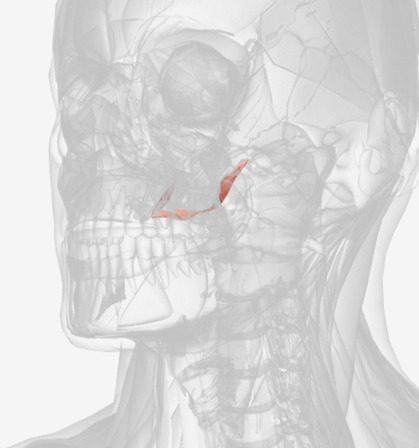

Tensor veli palatini

origin is on the sphenoid bone, coursing down to a tendon wrapping down around the pterygoid hamulus (of the sphenoid), then directed medially to the palatal aponeurosis; function is to dilate the Eustachian tube

Tensor Veli Palatini

|  |  |

Tensor veli palatini

C

Pterygoid hamulus

D